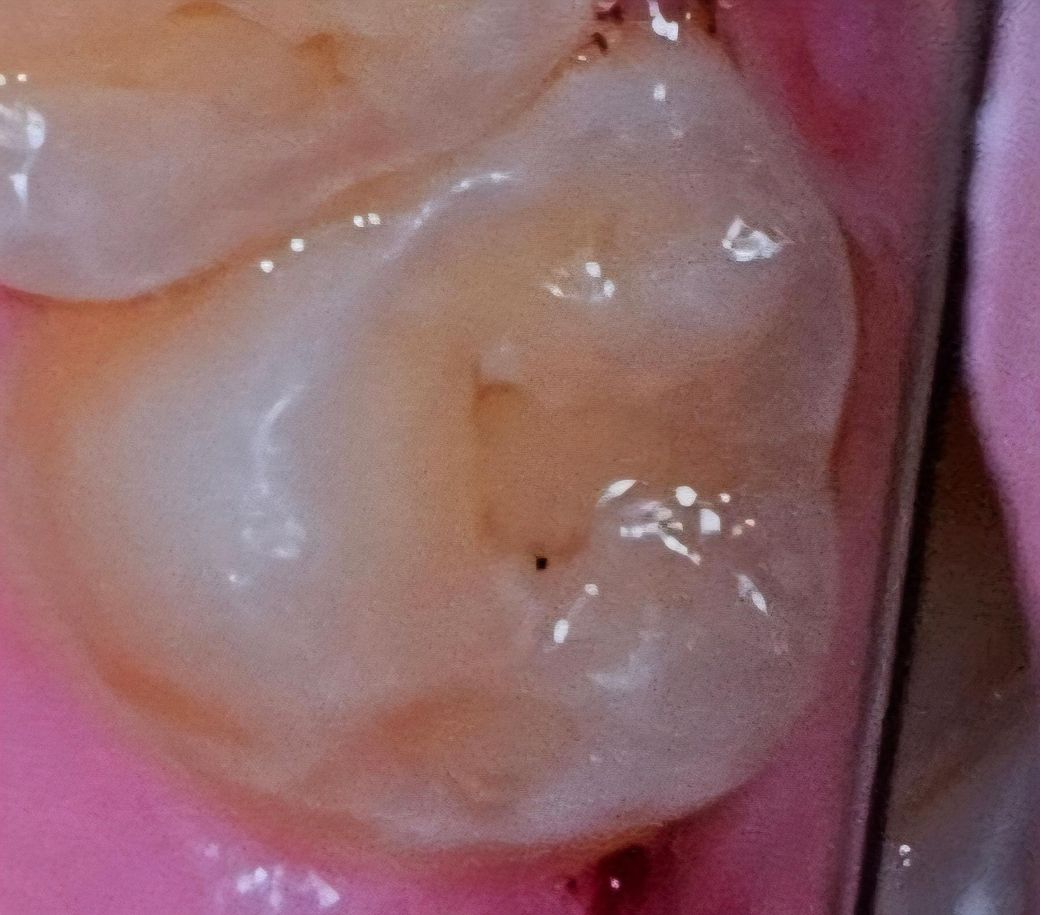

• 진단: 상악 좌측 제2대구치(#27) 치관 파절 (S02.53)

• #27(파절치): 사고 직후엔 없었으나, 귀가 후 찬물 섭취 시 찌릿한 지각과민(시림) 증상이 나타나고 있습니다.

• #26(인접치): 의사 소견상 미세 균열이 관찰되었으나, 진단서에는 "파절과의 연관성을 확정 지을 수 없음."이라 명시되었습니다.